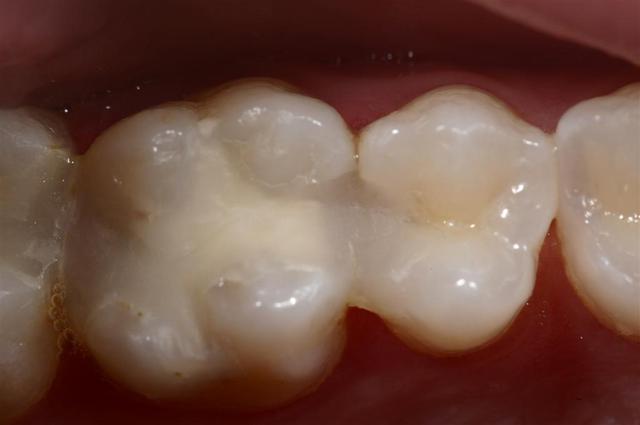

Une patiente, 24ans, à qui j'ai réalisé un composite il y a 2 ans se présente chez un confrère voisin durant mes congés pour des douleurs secteur 2.

Il réalise des "composites". Pas de matrice je pense, cavit en fond de cavité, aucune étanchéité...

Ces soins ont été réalisés il y a 2 mois, et la patiente à mal en permanence depuis...

Je vois la patiente hier en pulpite sur 27...

Faire une tranchée sur 3 dents mettre du cavit + compo et côter sc12 + sc17 + sc12. C'est criminel...

je vais laisser passer ma colère et garder ce genre d'iconographie dans un coin...